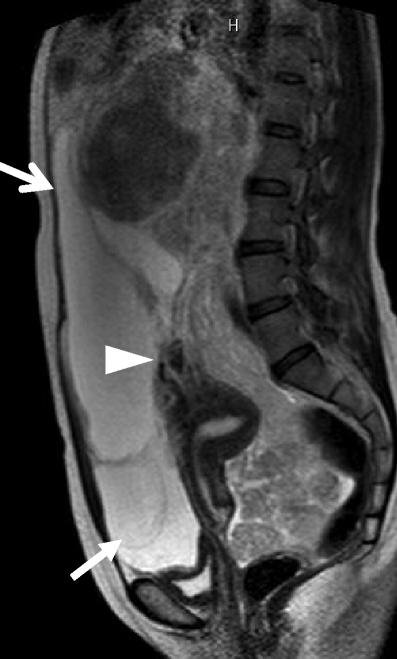

A huge subserosal leiomyoma in a 40-year-old woman. a Sagittal T2-weighted image demonstrates a huge heterogenous tumor consisting of cystic components of bright intensity anteriorly (arrows) and solid component of intermediate to low intensity. Note the tumor vessels extending from the myometrium to the tumor (arrowhead)